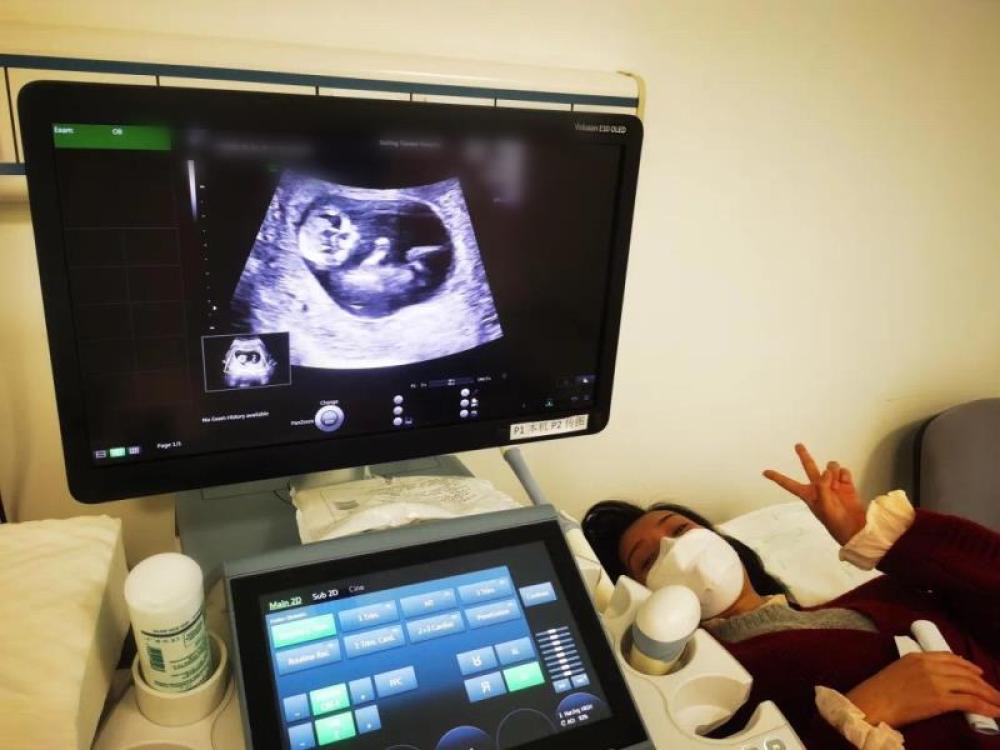

今天一早,妻子去醫(yī)院進(jìn)行B超檢查,同事用手機(jī)拍攝下了B超顯示屏上的畫面,記錄下了這個(gè)87天的小家伙第一次“亮相”。

圖為北京天壇醫(yī)院袁磊愛人做B超檢查。

“袁磊,看看你們家寶寶,可愛嗎?”收到同事發(fā)來的視頻,第一眼就看哭了,身邊的同事看完視頻也哭了。

視頻里,這個(gè)小家伙好像聽到了外面的召喚,在媽媽的肚子里伸手、踢腿、翻身,用各種動(dòng)作進(jìn)行回應(yīng)……看到他那小胳膊小腿,一種從未有過的幸福感不停地向上涌,眼淚怎么也控制不住。

其實(shí)在武漢這么多天,他一直就是我的牽掛,今天終于看到他了,那種感受真是又緊張又激動(dòng),雖然還看不清他的樣子,但是已經(jīng)感受到他的活力。